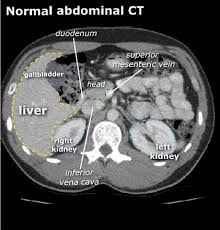

CT scan adalah prosedur pemeriksaan yang menggunakan komputer dan mesin X-ray. Siapkan dana lebih 20-30 lebih untuk biaya yang tidak terduga. An abdominal CT scan helps your doctor see the organs blood vessels and bones in your abdominal cavity.

1000000 hingga lebih dari Rp. A CT scan is a medical imaging tool that allows doctors to see bone organs and soft tissues inside a persons body. Tim ahli medis kami siap memandu Anda memilih tindakan USG Perut yang paling tepat. An abdominal CT scan helps your doctor see the organs blood vessels and bones in your abdominal cavity. A CT scan of the abdomen may be performed to assess the abdomen and its organs for tumors and other lesions injuries intra-abdominal bleeding infections unexplained abdominal pain obstructions or other conditions particularly when another type of examination such as X-rays or physical examination is not conclusive. Mamografi Tanyakan Harga Lihat harga bandingkan hasil. Berdasarkan tujuan dan manfaatnya beragam jenis CT Scan mulai dikembangkan antara lain. 1000000 hingga lebih dari Rp. A mass in your abdomen that can be felt.